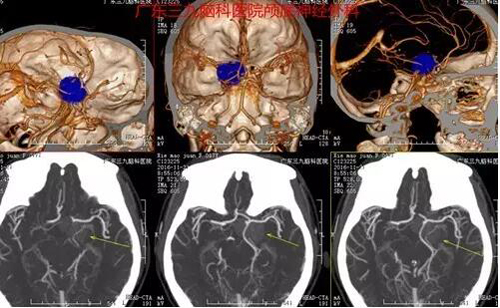

图1:术前CT提示:左侧海绵窦旁稍高均匀密度影

图2:术前CTA提示其内少许细小血管,左侧颈内动脉海绵窦段受包绕